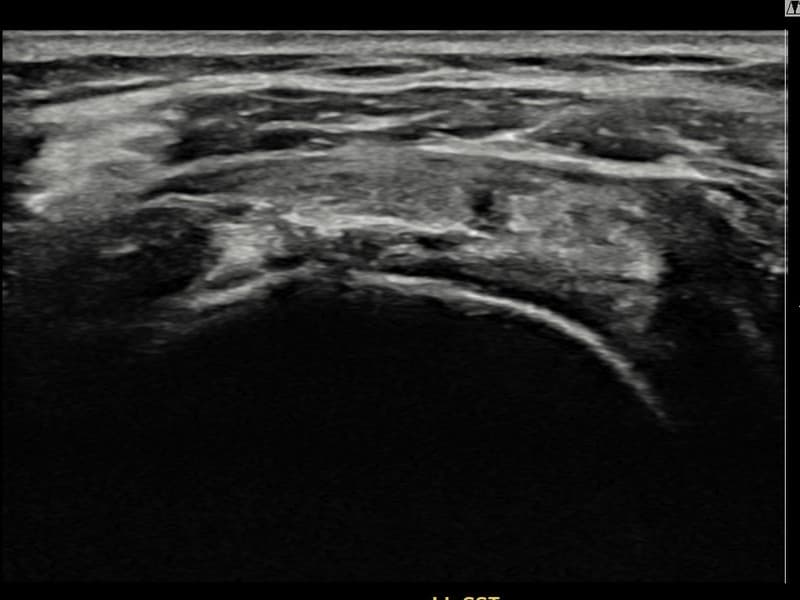

术后

术前超声确认左侧 冈上肌腱 滑囊面侧部分撕裂,左侧冈上肌腱回声不连续伴肌腱缺损(14mm × 7mm (肌腱厚度约65%缺损))。术后超声显示撕裂部位充满再生组织,肌腱连续性恢复,回声模式正常化。